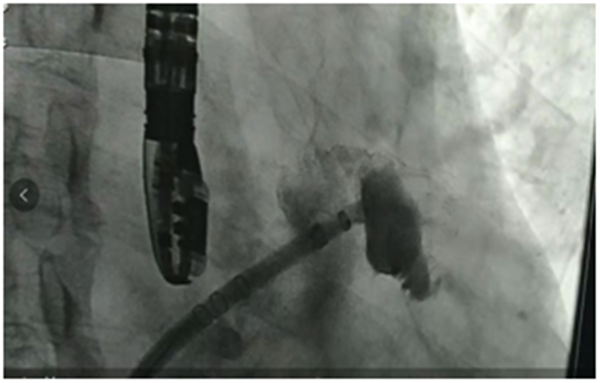

术中TEE测量心耳大小00 18mm×30mm,450 20mm×33mm, 90018mm×30mm, 135017mm×18mm,DSA测量心耳开口22mm,深度27mm。 根据TEE及DSA测量的结果,综合考虑后,选用27mm WATCHMAN左心耳封堵器,伞器展开后,测量计算压缩比为19%-25%,牵拉稳定,满足PASS原则,释放器械,成功封堵。

房颤治疗的目的是消除房颤、控制症状、预防卒中。房颤预防卒中是根本。我院成功开展左心耳封堵术,实现了导管消融节律控制及左心耳封堵预防卒中双治疗手段实现的突破,为更多房颤患者健康保驾护航。